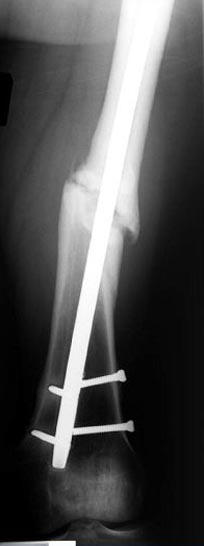

Аппарат Илизарова= Taylor spatial frame

Гвоздь для ротационных смещениц был бы идеальнымимплантом, после коррекции есть возможность блокировать, но из-за укорочения метод оставил на последнее место. Есть метод Сhaplan лечения ложных суставов бедра, где необходимость bone graft, накладывается феморальный дистрактор и после удаления штифта - рассверливание, через проксимальный канал вводят костный графт в место ложного сустава под рентген контролем, потом вводят штифт, кстати, само рассверливание дейстивует как стимулятор - активизирует восстановительный процесс.

Операцию провели в два этапа, сперва удалили штифт, рассверливание римером на пару мм большего диаметра, определение чувствительности на анаэробную и аэробную культуру (где исследования показали негативный результат чувствительности), через дней десять - начали аппаратную фиксацию.